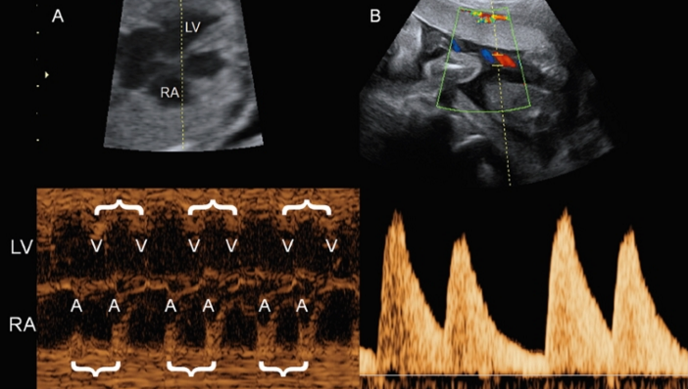

農曆年前最後一次OB會由禾宜婦幼診所的呂政忠醫師打頭陣。呂醫師分享一例複雜的先天性心臟病,從不對稱的四腔室切面引起左心發育發育不全的第一印象出發,用segmental approach的思維帶領聽眾從心房心室的辨識、大動脈的連結,一路抽絲剝繭推論出主動脈弓中斷的診斷。

圖一 呂政忠醫師報告Dextrocardia IAA

呂醫師在案例後的討論也針對內臟錯位(Heterotaxy syndrome)常用的描述名詞,及容易合併的異常做了清楚的資料補充。